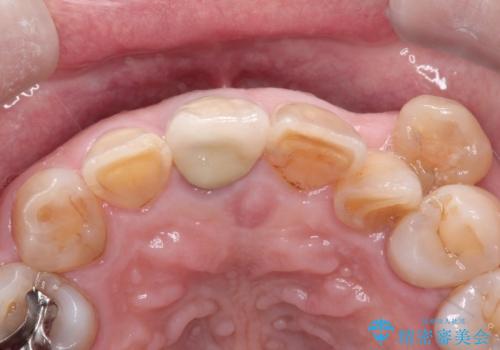

セラミックによる前歯の変色の改善

- 前歯の色が変色してきて、気になるとのことで来院されました。

オールセラミックを装着することで改善することとしました。

他の歯になじむ色を選択することで、自然な仕上がりにすることができました。